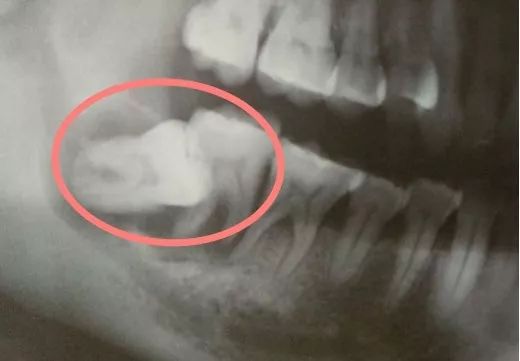

智齿长歪了:智齿向前倾倒可以顶坏邻牙,严重可能导致邻牙牙根或周围牙槽骨吸收,两颗共赴黄泉。向口腔侧壁和舌侧倾倒的智齿则容易摩擦颊黏膜或舌头,引起溃疡或其他病变。

智齿向前倾,顶坏了前面的牙齿丨作者供图